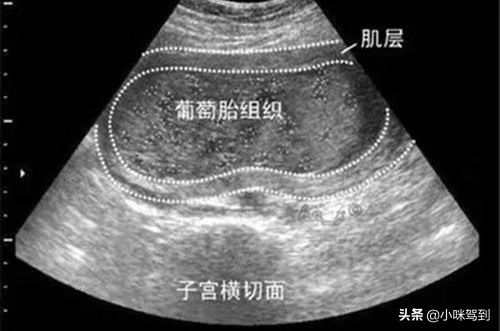

葡萄胎是受精卵体着床在子宫壁,胎盘的绒毛滋养细胞异常增生,胚胎细胞间质增大,出现了泡水样的细胞团,一个细胞团连着一个细胞团,像葡萄一样,一串一串的,所以也称为葡萄胎。名字好听却是有毒!如果不及时清除,细胞侵蚀子宫肌层变成侵蚀性葡萄胎,甚至最终可能变成绒毛膜癌。

如果怀的是葡萄胎,到医院可以通过x片、阴道分泌物涂片或者B超可以检查出来。如果是葡萄胎,胎儿是没有胎心,B超显示是雪花状或者蜂窝状。除了这些,孕妇也可在家进行自我监测,学会区别正常的妊娠和葡萄胎,一发现异常及时到医院进行治疗。

B超下的葡萄胎